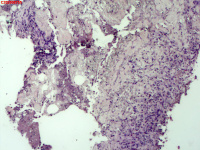

| 图片: | |

- 右侧胸壁穿刺组织活检

| 性别 | 女 | 年龄 | 81岁 | 临床诊断 | 胸锁关节结核? |

| 一般病史 | 胸部CT示:右肺下叶小结节,建议3-6个月复查,必要时胸外科会诊。左肺上叶多发小斑点、结节影,结核可能。右肺上叶多发点状影。双肺间质性改变。纵隔淋巴结肿大、钙化。右侧胸锁关节见骨质破坏,周围见软组织肿胀。 | ||||

| 标本名称 | 右侧胸壁穿刺组织活检 | ||||

| 大体所见 | B超:体表包块彩超示右侧胸壁混合回声包块,右侧胸壁低回声区,CDFI示:其内未见明显血流信号。 | ||||